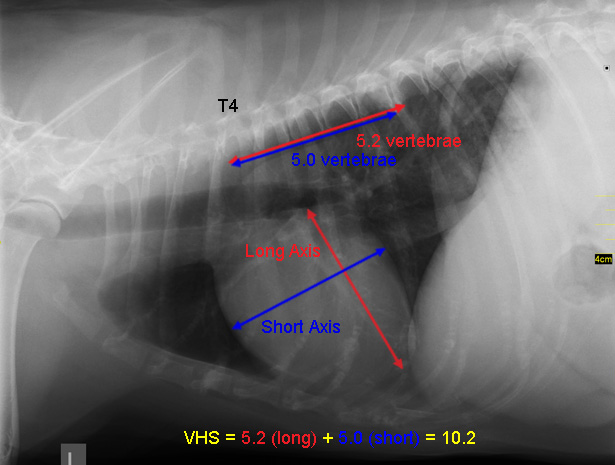

• VHS measurements to detect enlargement

The Vertebral Heart

Size or Scale or Sum (VHS) is an objective means of measuring

heart size.

As

the x-ray image above shows, using calipers, they

measure the length (from the apex to the bottom of the left mainstem) and width

(at

its widest point perpendicular to the lemgth measurement) of the heart

on a lateral x-ray and compare those dimensions

to the number of veterbrae from T4 to T12, to calculate the VHS value. Since

the dog's own vertebrae are used for comparison, each VHS value is

normalized to the dog's overall body size.

See

this

YouTube video for details. A diagram showing how the VHS is calculated

is

here. This is called the Buchanan VHS method, devised

by Dr. James W.

Buchanan, a pioneer in the research of MVD in cavaliers, in

1995. See his

1995 article.

The VHS is not intended to diagnose CHF. It's purpose is to enable veterinarians to more accurately determine enlargement of the heart (called cardiomegaly or dilation) and the progression at which the enlargement is occurring, which usually is due to MVD. However, since MVD normally initially causes only the left atrium (LA) to enlarge, the VHS method is not precise enough to measure only the size of the LA. See for example, the x-ray at left, which shows that the VHS measurements entirely miss the bulbous enlarged LA in the upper right corner of the heart. (Image from Hezzell, 2018.)

The VHS method is most effective when it is used to compare two x-rays of the same dog's heart, taken over time, to see if the later x-ray's VHS value is higher than the earlier one, thus indicating that an enlargement of the heart has occurred. Therefore, once an MVD murmur is first detected, it is advisable to obtain an initial set of chest x-rays (called a "baseline" set) for comparison with subsequent x-rays once progression of the MVD is suspected.

An increase in VHS value of >0.1 per month over six months or more, in combination with a VLAS value >3.0, (see VLAS below) is evidence that the patient's heart has enlarged enough to classify it in Stage B2.

The VHS values of cavaliers which do not have any heart enlargement can vary widely. In a 2001 study of 20 CKCSs and a 2005 study of 50 of them, researchers found that the normal range of VHS values for cavaliers was from 10.0 to 11.7. In an October 2018 article, a cavalier with a normal-sized heart with a VHS value of 11.9 was reported. In an October 2023 article in which 167 CKCSs with normal-sized hearts were examined, their VHS values ranged from 8.5 to 12.5. These wide ranges of normal-sized VHS values make efforts to diagnose heart enlargement with a single set of x-rays pointless, unless the VHS value is above 12.5.